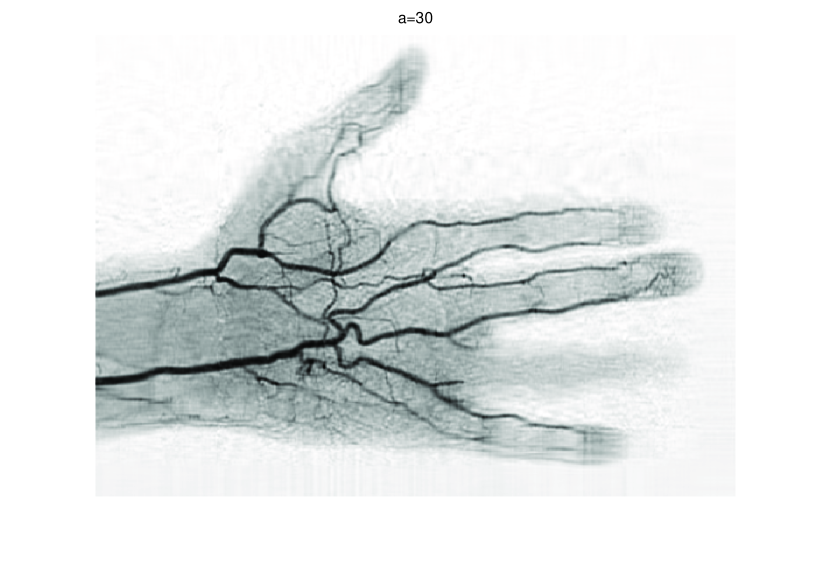

In this subsection, we demonstrate performances of ISVTA on image inpainting problems. The ISVTA is tested on some medical grace images (255×192255192255\times 192 Brain angiography image (BAI), 395×549395549395\times 549 Hand angiography image (HAI) and 419×400419400419\times 400 Intracranial venous image (IVI)). We use the SVD to obtain their approximated low-rank images with rank r=30,40,30𝑟304030r=30,40,30, respectively. Numerical results of ISVTA for theses low-rank image inpainting problems are reported in Table 5, 6, 7, 8.

Refer to caption

Figure 4: Original 395×549395549395\times 549 HAI and its approximation with rank 40.

Table 5, 6 show that ISVTA performs powerful in finding a low-rank matrix on image inpainting problems. Indeed, we could get an exact low-rank image by the ISVTA by choosing proper a𝑎a. Moreover, it is necessary to point out that our method does not work well for all a>0𝑎0a>0, and we can find that a=100𝑎100a=100 is not a good strategy for the low-rank IVI either SR=0.40SR0.40\mathrm{SR}=0.40 or SR=0.50SR0.50\mathrm{SR}=0.50. The numerical results of ISVT, SVTA and SVPA compared in Table 5, 6, 7, 8, 9, 10 under same circumstance show that the ISVT algorithm performs far more better than ISTA and SVPA on image inpainting problems for some proper a>0𝑎0a>0.